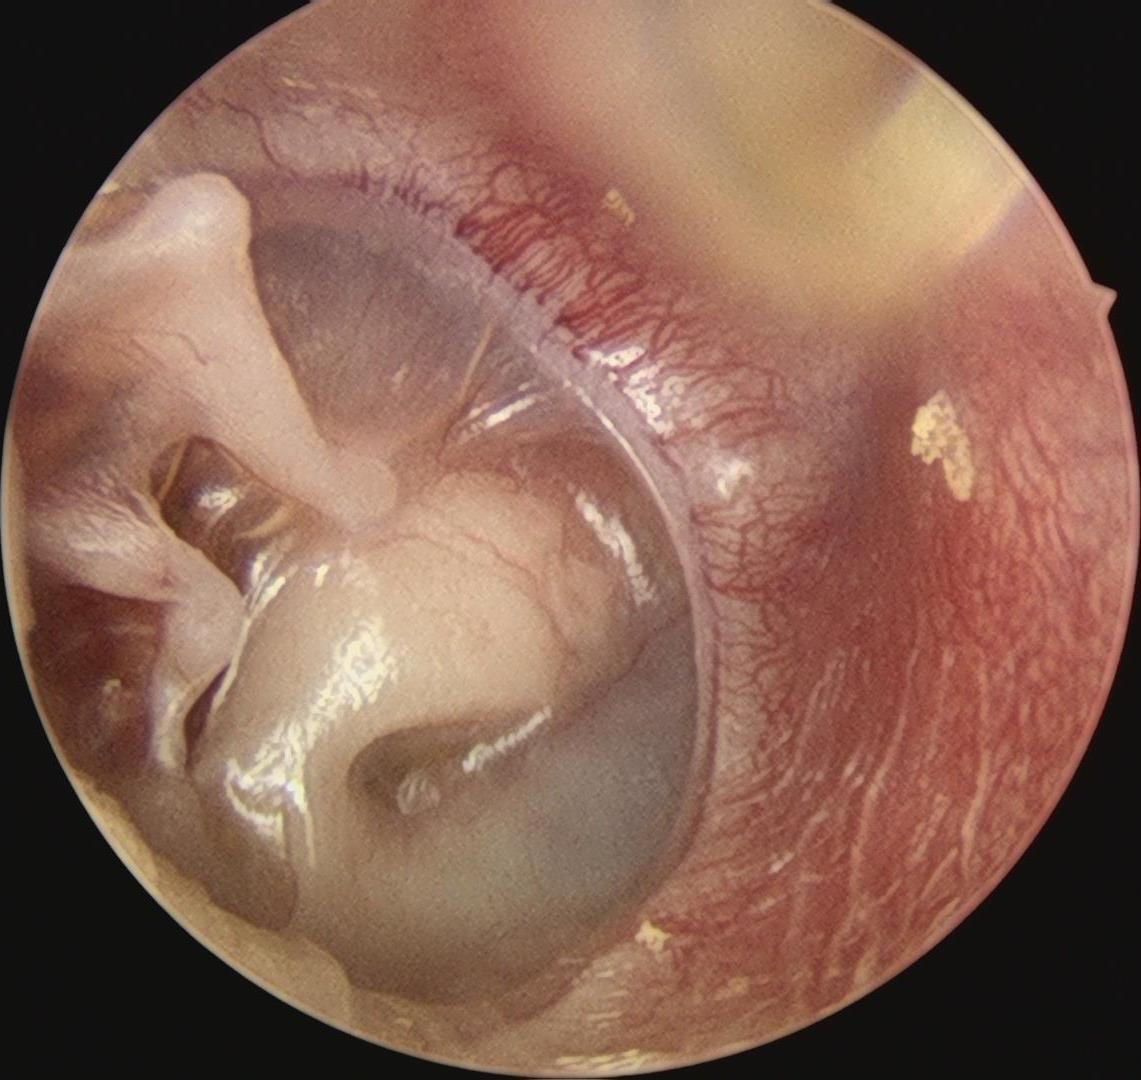

通过好大夫互联网医院预约好住院后,小尹和妈妈顺利入住了禅医耳鼻喉科。做完术前评估后,梅晓峰主任、郑立岗主任和耳鼻喉团队认真评估了小尹的病情,双侧重度粘连性中耳炎,右侧比左侧严重,这次建议做右侧,采用耳内镜微创技术,可以最大限度的保留所有的中耳结构,对孩子的一生都是非常有好处的。

手术由郑立岗主任亲自主刀,由于孩子的右侧鼓膜内陷得非常严重,手术的难度非常大,要从听骨链和鼓室内侧壁完整地剥离上皮组织,是一个非常精细的操作,没有十年的精细操作功夫是非常难成功完成的。郑主任在这方面有比较多的成功手术经验,所以整个的过程是非常顺利的,完整翻起了内陷的上皮组织。但孩子的砧镫关节术中看还是被内陷的上皮腐蚀断裂了,由于孩子比较小,郑主任并没有用人工听骨。而是采用了自体听骨对接的新技术,把断裂的听骨接在了一起。整个手术做了130分钟,非常的顺利。术后查房患者无明显的不适,无手术并发症。